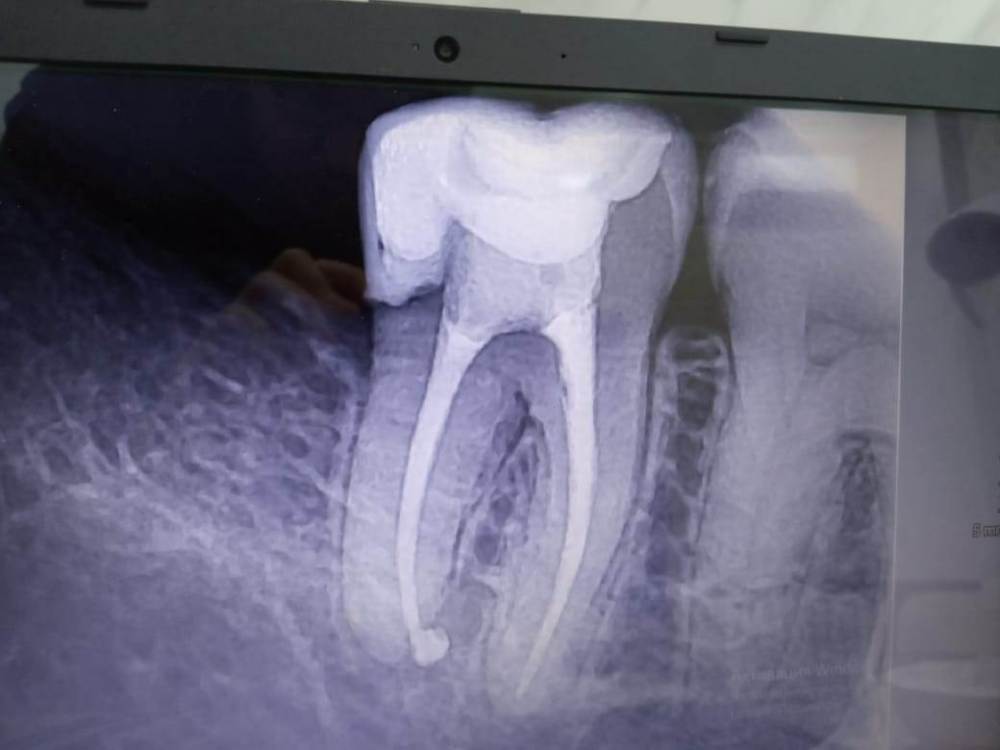

Вот снимки, но врач сказал, что снимкам не стоит на 100% доверять. Болит зуб или даже зубы при употреблении пищи, а также присутствует временами постоянное нытье зуба / зубов. Что делать, я и врачи (ходил к нескольким) совершенно не понимаем. Дело в том, что определить кто именно виновник, трудновато. В одном из зубов удален нерв, и при надавливании чувствуется, что ему некомфортно. Но не факт, что виновник проблем именно он... В интернете упомянул кто-то компьютерную томографию, которая стоит недешево. Скажите, стоит ли ее делать и как она поможет?